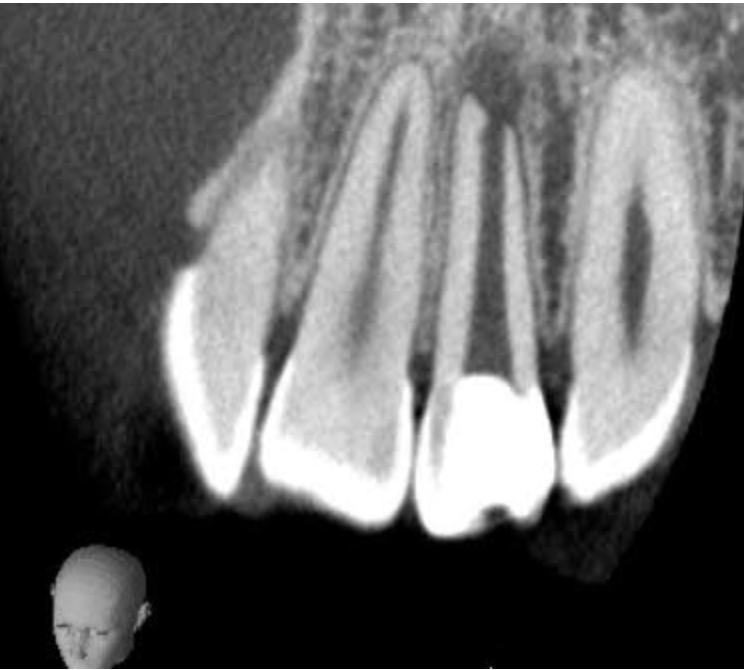

こちらが根尖切除術を行なった左上2番(治療前)です。

次の写真は根尖切除術後3ヶ月後で、根尖が順調に治癒し骨が再生してきています。